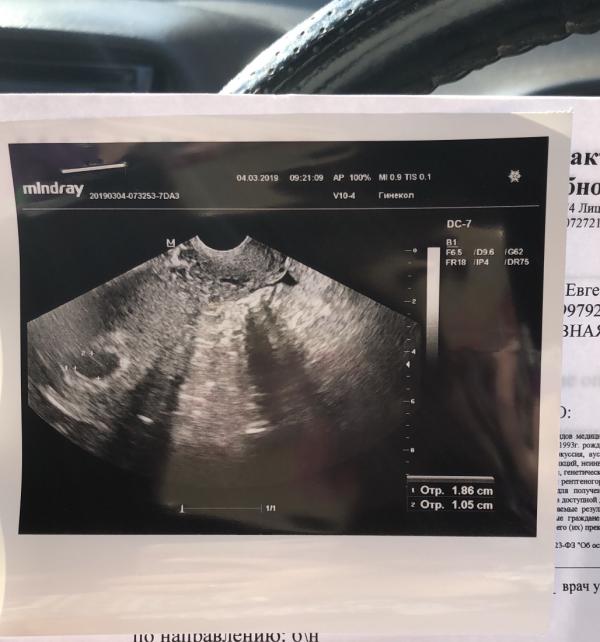

Так все хорошо начинается, надеюсь так и продолжится. Жуткие переживания как и у всех беременных.

Даже мысли до жути тупые лезут в голову🤯😁 (когда в первый месяц у нас не случилась беременность, а так хотелось, я даже задумалась, а если у меня матка?! Ведь во вторые роды все шло не очень и может злые врачи мне ее того, удалили, да не сказали? 😁😁😁😁🤦🏽♀️🤦🏽♀️🤦🏽♀️🤦🏽♀️ Это просто жесть, хорошо что уже чер...